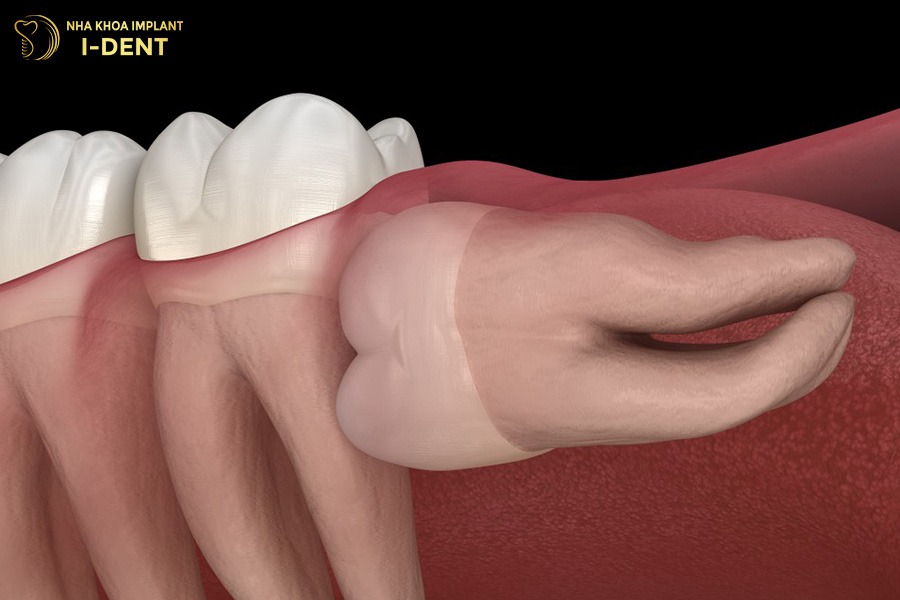

- Răng khôn mọc lệch đẩy răng khác

Răng khôn (răng số 8) khi mọc lệch có thể gây áp lực đẩy các răng khác ra khỏi vị trí đã được sắp xếp sau khi niềng. Vì vậy, hầu hết các bác sĩ chỉnh nha đều khuyến nghị nhổ răng khôn trước khi bắt đầu niềng răng hoặc trong giai đoạn đầu của quá trình điều trị, có thể cân nhắc giữ lại nếu răng mọc thẳng tuy nhiên điều này khá hiếm gặp. Lợi ích của việc nhổ răng khôn trước khi niềng là ngăn ngừa tái phát sau điều trị.